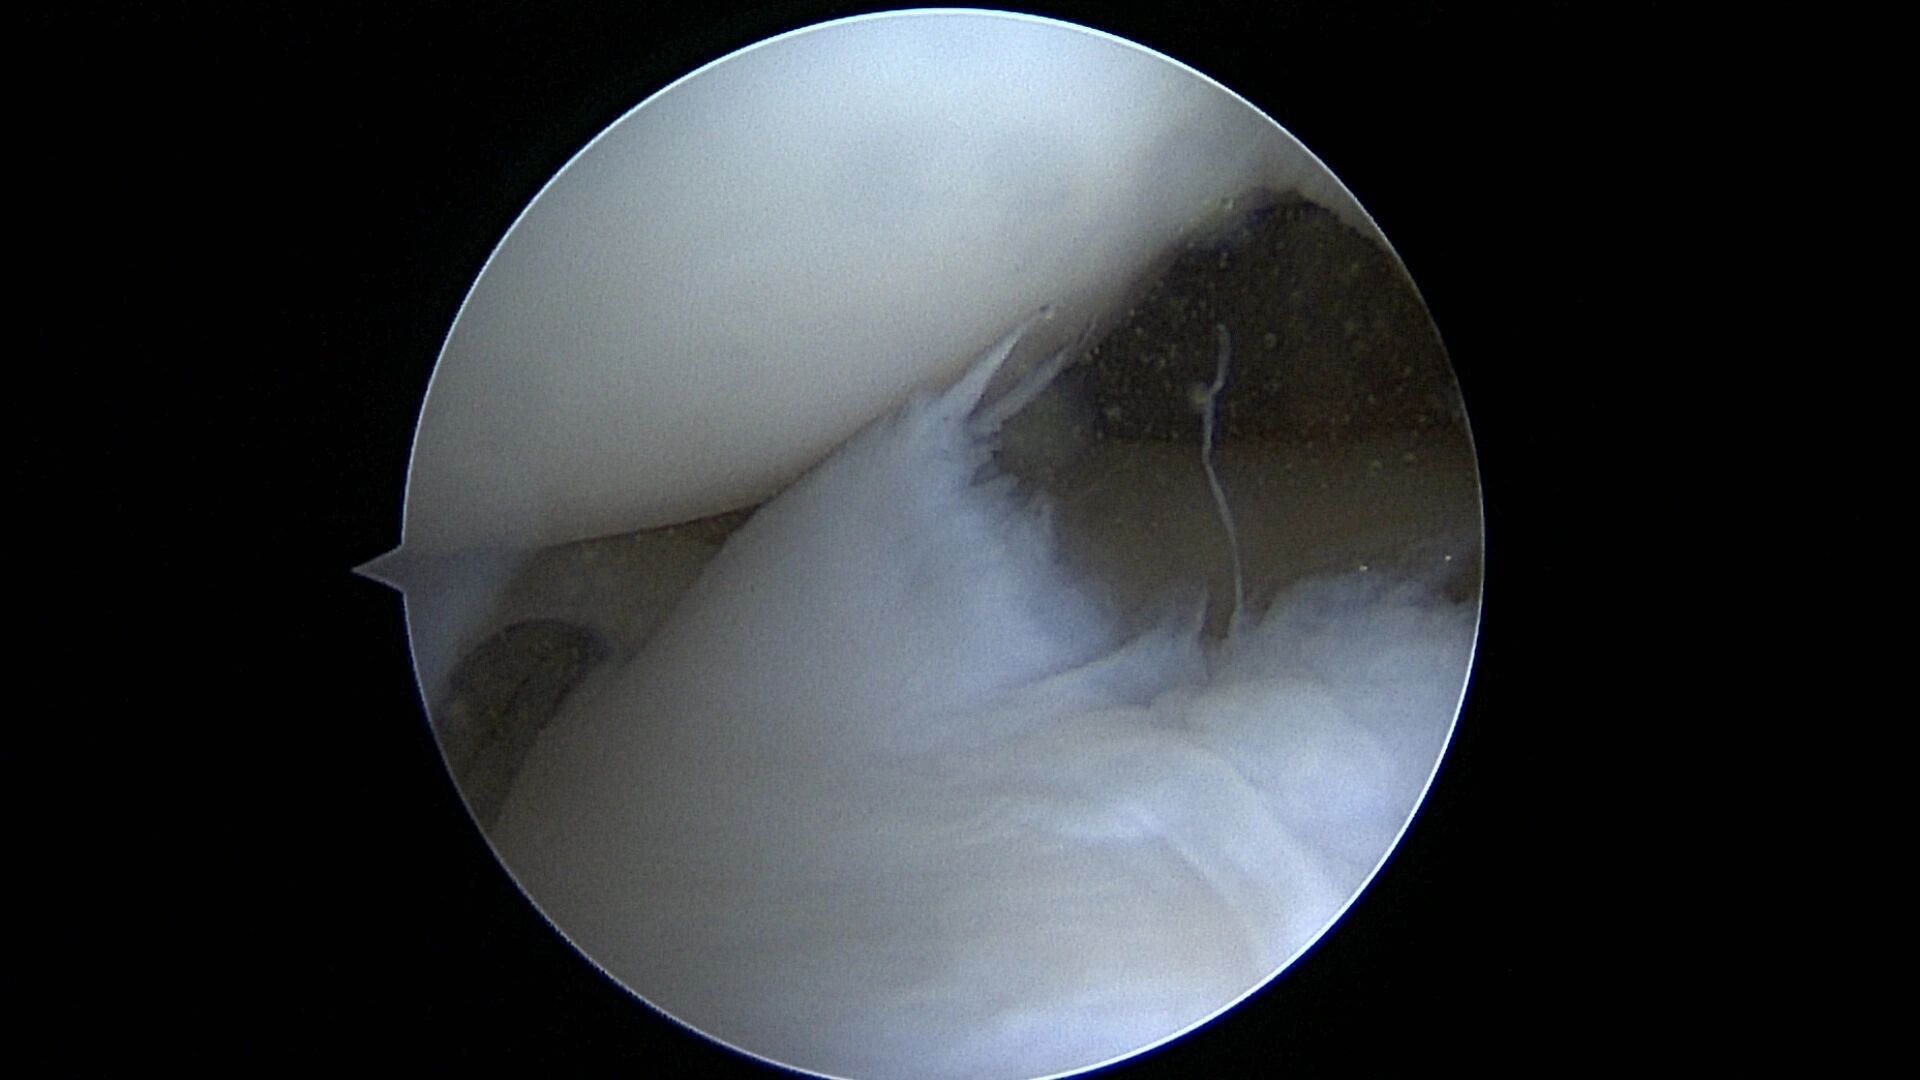

- Meniscus Surgery

- Meniscus Surgery 2